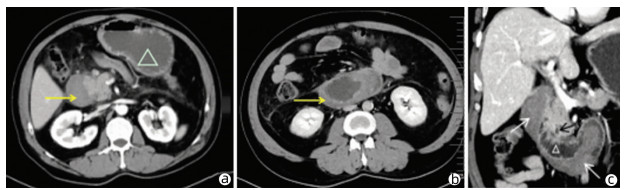

Research advances in peripheral vascular invasion of hepatic alveolar echinococcosis

Han LI, Lizhao HOU

2022, 38(3): 719-723. DOI: 10.3969/j.issn.1001-5256.2022.03.046

Abstract(1150) HTML (294) PDF (1964KB)(43)

Abstract:

Alveolar echinococcosis proliferates in the form of chronic infiltration and has no obvious symptoms and signs in the early stage, and when attending the hospital, some patients already have one or more complications and invasion of important intrahepatic vessels and bile ducts. The research on peripheral vascular invasion of alveolar echinococcosis may help to determine the best individualized treatment and thus improve the cure rate and prognosis of patients. This article reviews the pathological mechanism, clinical manifestations, imaging, clinical classification, and treatment of alveolar echinococcosis.